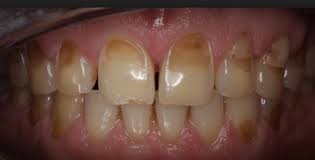

Tooth Enamel Erosion

What is tooth enamel?

Enamel is the thin outer covering of the tooth. This tough shell is the hardest tissue in the human body. Enamel covers the crown which is the part of the tooth that's visible outside of the gums.

Because enamel is translucent, you can see light through it. But the main portion of the tooth, the dentin, is the part that's responsible for your tooth color -- whether white, off white, grey, or yellowish.

Sometimes coffee, tea, cola, red wine, fruit juices, and cigarettes stain the enamel on your teeth. Regular visits to your dentist for routine cleaning and polishing can help remove most surface stains and make sure your teeth stay healthy.

What does tooth enamel do?

Enamel helps protect your teeth from daily use such as chewing, biting, crunching, and grinding. Although enamel is a hard protector of teeth, it can chip and crack. Enamel also insulates the teeth from potentially painful temperatures and chemicals.

Unlike a broken bone that can be repaired by the body, once a tooth chips or breaks, the damage is done forever. Because enamel has no living cells, the body cannot repair chipped or cracked enamel.metimes coffee, tea, cola, red wine, fruit juices, and cigarettes stain the enamel on your teeth. Regular visits to your dentist for routine cleaning and polishing can help remove most surface stains and make sure your teeth stay healthy.

What are the environmental causes of tooth surface erosion?

Friction, wear and tear, stress, and corrosion (or any combination of these actions) can cause erosion of the tooth surface. More clinical terms used to describe these mechanisms include:

Attrition. This is natural tooth-to-tooth friction that happens when you clench or grind your teeth such as with bruxism, which often occurs involuntarily during sleep.

Abrasion. This is physical wear and tear of the tooth surface that happens with brushing teeth too hard, improper flossing, biting on hard objects (such as fingernails, bottle caps, or pens), or chewing tobacco.

Abfraction. This occurs from stress fractures in the tooth such as cracks from flexing or bending of the tooth.

Corrosion. This occurs chemically when acidic content hits the tooth surface such as with certain medications like aspirin or vitamin C tablets, highly acidic foods, GERD, and frequent vomiting from bulimia or alcoholism.

What are the signs of enamel erosion?

The signs of enamel erosion can vary, depending on the stage. Some signs may include:

Sensitivity. Certain foods (sweets) and temperatures of foods (hot or cold) may cause a twinge of pain in the early stage of enamel erosion.

Discoloration. As the enamel erodes and more dentin is exposed, the teeth may appear yellow.

Cracks and chips. The edges of teeth become more rough, irregular, and jagged as enamel erodes.

Severe, painful sensitivity. In later stages of enamel erosion, teeth become extremely sensitive to temperatures and sweets. You may feel a painful jolt that takes your breath away.

Cupping. Indentations appear on the surface of the teeth.

When enamel erodes, the tooth is more susceptible to cavities or tooth decay. When the tooth decay enters the hard enamel, it has entry to the main body of the tooth.

ow is tooth enamel loss treated?

Treatment of tooth enamel loss depends on the problem. Sometimes tooth bonding is used to protect the tooth and increase cosmetic appearance.

If the enamel loss is significant, the dentist may recommend covering the tooth with a crown or veneer. The crown may protect the tooth from further decay.